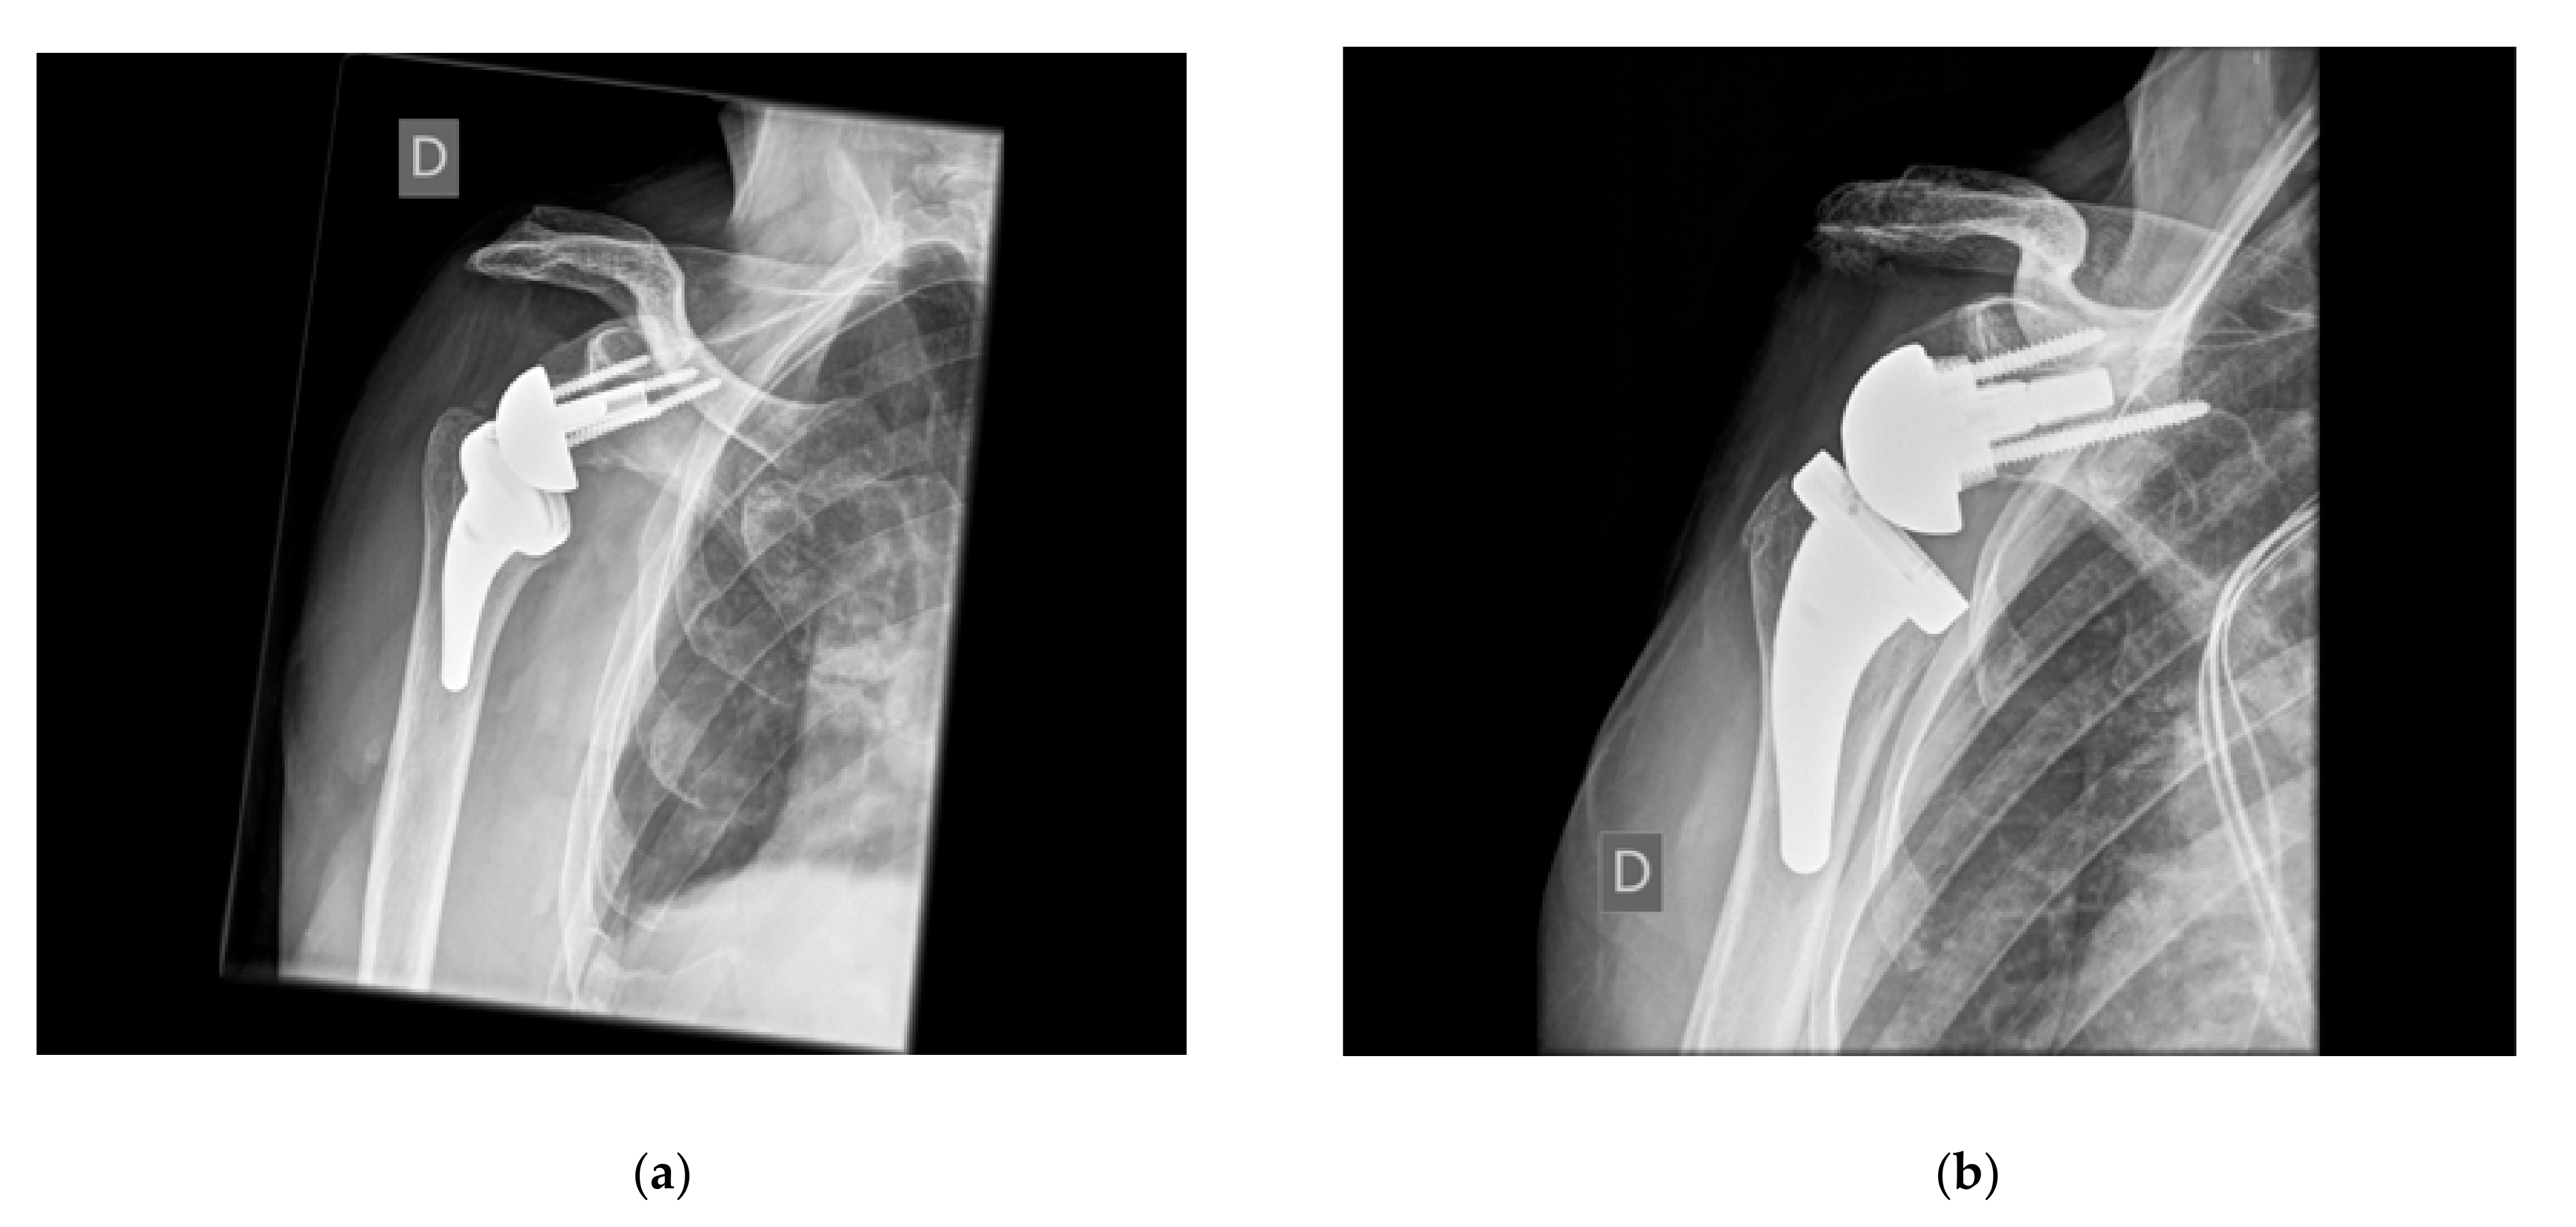

4.2. Humeral Lateralization

4.2.1. Advantages of Humeral Lateralization

4.2.2. Disadvantages of Isolated Humeral Lateralization

4.3. How Much to Lateralize?